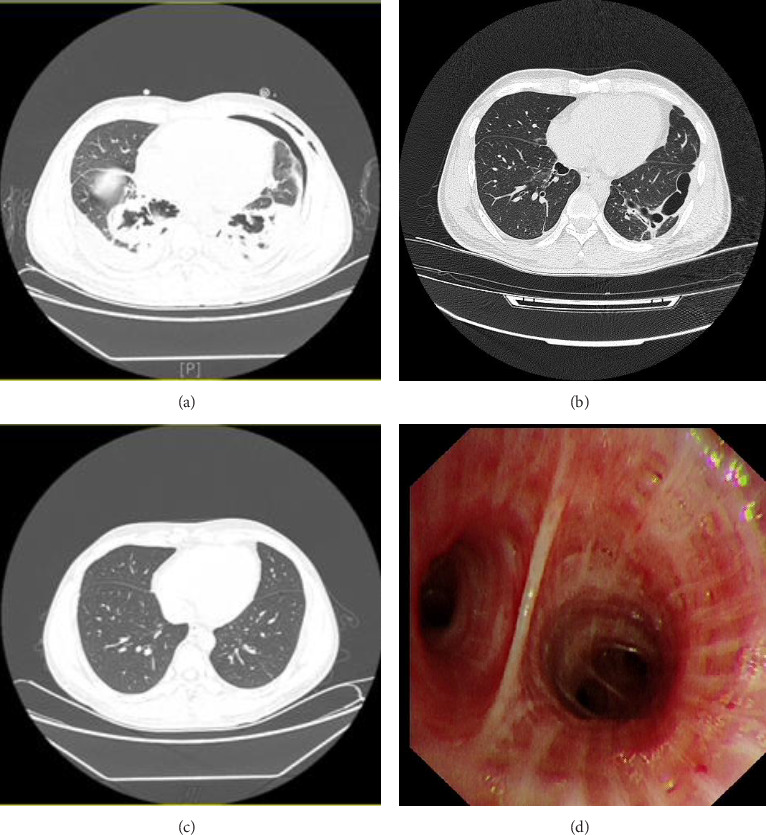

Exogenous lipoid pneumonia (ELP) is a rare disease with both acute and chronic forms. This paper primarily summarizes the diagnosis and treatment process of bronchoalveolar lavage combined with glucocorticoids treatment of acute ELP caused by aspiration of liquid hydrocarbons (e.g., kerosene and diesel fuel) at our hospital. Furthermore, the present study analyzes the advantages of bronchoalveolar lavage combined with glucocorticoids treatment of acute ELP.